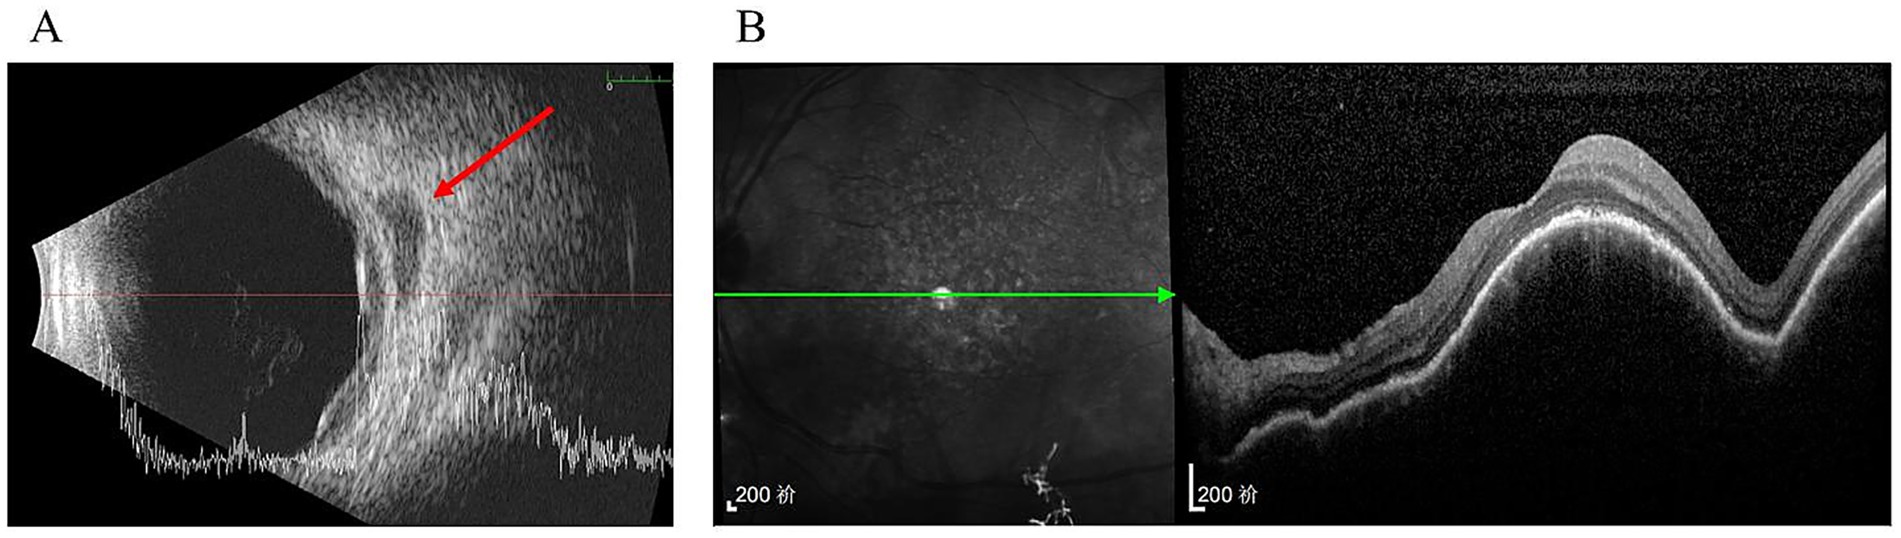

Three months later, ultrasonography demonstrated only slight enlargement of the choroidal thickening region and hypoechoic area (Figure 2A). Furthermore, OCT imaging at the macula showed no significant changes compared with the previous scan (Figure 2B).

Figure 2

Three months after the initial presentation. (A) Ultrasonography showed the area of diffuse choroidal thickening and retrobulbar hypoechoic area were slightly increased (arrow); (B) No significant change in the performance of OCT compared with the presence of last time.